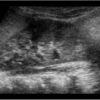

– Thận xoa trục, 2 cực dưới thận liên tục với nhau vắt ngang qua phía trước cột sống bởi nhu mô thận hay tổ chức xơ.

– Trên lát cắt dọc: không thấy rõ ranh giới cực dưới 2 thận.

– Trên lát cắt ngang qua đường giữa: 2 thận dính nhau, vắt ngang qua cột sống, phía trước động mạch chủ bụng.

– Có thể kèm theo các bất thường bất thường đường bài xuất, thận đôi, sỏi, nang thận hoặc u thận, sỏi gây giãn đường bài xuất.

=> Case lâm sàng 2: